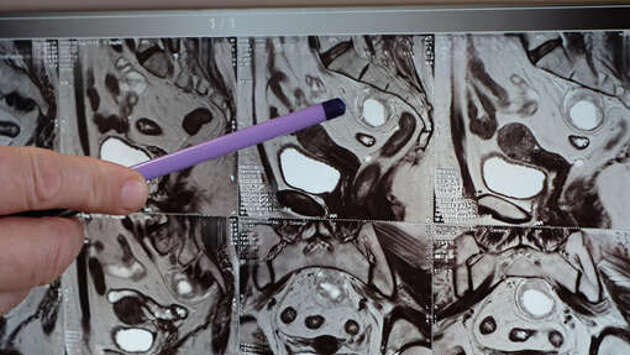

Пожилой россиянке удалили врожденную кисту между копчиком и прямой кишкой, которая могла остаться от недоразвитого эмбриона. Об этом сообщается в Telegram-канале Амурской областной клинической больницы (АОКБ). У 66-летней женщины диагностировали пресакральную кисту – аномальную полость в области между копчиком и прямой кишкой. "Это довольно редкая патология. Будучи врожденной, она долгие годы не дает о себе знать. Согласно одной из теорий, эта киста – ничто иное как второй эмбрион, который не развился", — рассказал заведующий проктологическим отделением АОКБ Андрей Симоненко. Пресакральная киста может переродиться в злокачественное образование, избавиться от нее можно только с помощью хирургии. Врачи АОКБ провели лапароскопческое вмешательство, которое позволило пациентке быстрее восстановиться, избежать осложнений и встать на ноги в день операции. До этого мужчине в Подмосковье удалили опухоль, из-за которой увеличившаяся в 20 раз простата затруднила отток жидкости из мочевого пузыря.